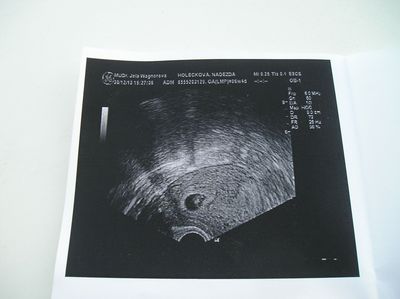

Tak holky pro info jsem od soboty v nemocnici nasly mi hematom tak co se mi stalo minuly mesic tak si me tu nechaly uz vubec nespinim zitra jdu na dalsi utz jinak mimik tam je vse jak ma byt ma uz srdicko urcite vam sem pak dam foto dneska je to 7tt

@barborynka Tak jen pekne lez a odpocivej, hematom se urcite vstreba a vse bude ok. Drzim palce!